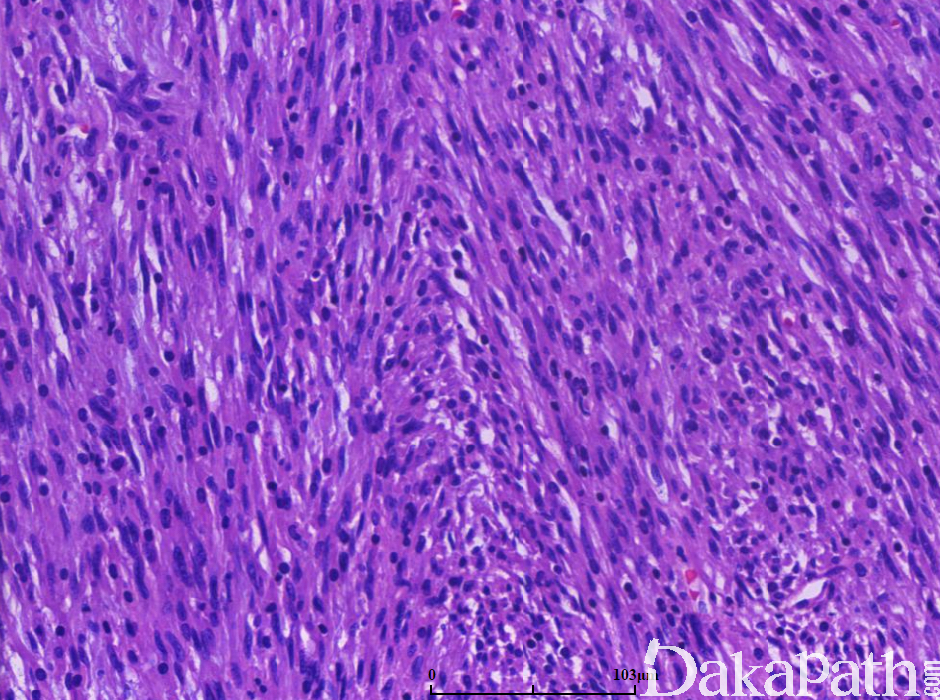

由纤维母细胞样细胞组成的恶性肿瘤,瘤细胞呈交织的条束状排列,可见鱼骨样排列结和不等量的胶原纤维。

镜下见瘤细胞常呈交织的束状排列,可见鱼骨样或呈人字形排列结构;

分化好的肿瘤,瘤细胞密度低,核轻度异型性,似纤维瘤病样,分化较差者瘤细胞稠密、肥胖,核染色深,染色质颗粒状,甚至呈片状增生的圆形或卵圆形细胞;

瘤细胞间可见多少不等的胶原纤维;